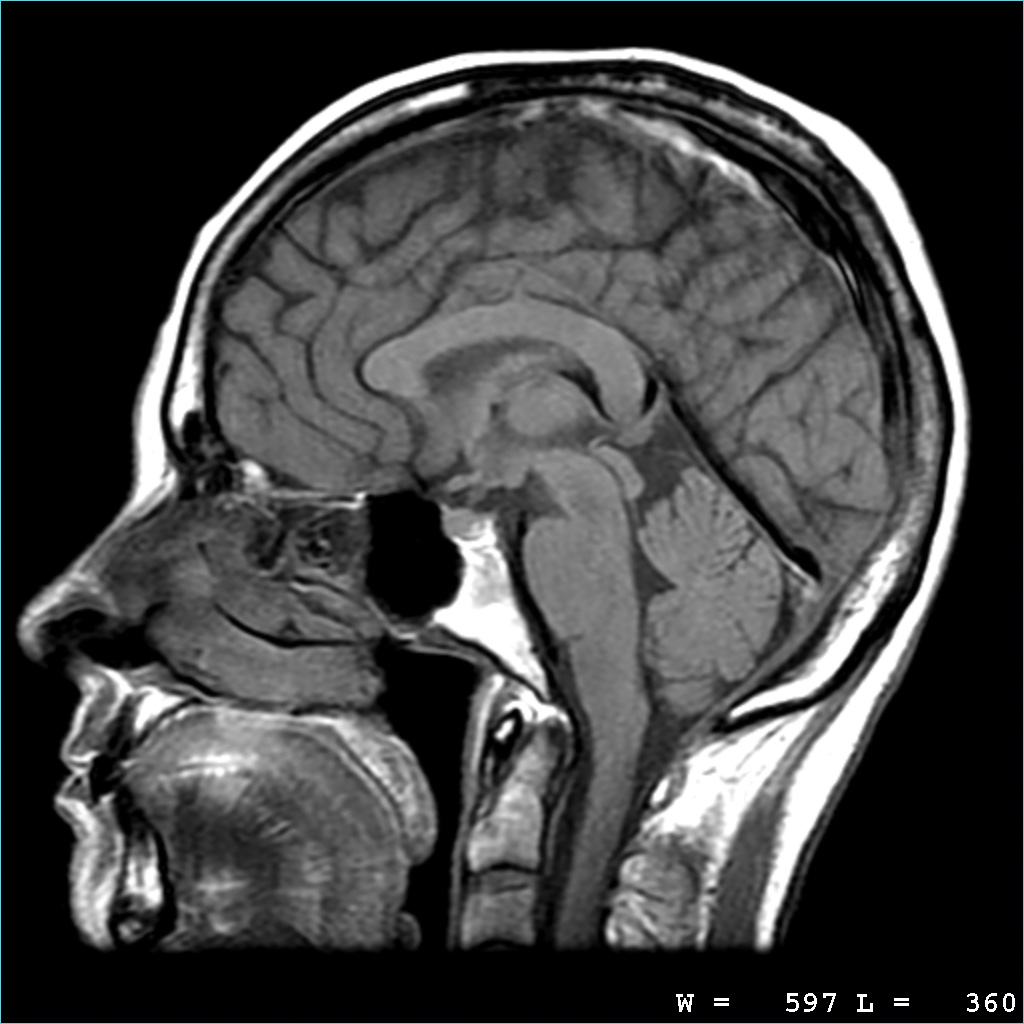

3. Identify normal anatomical features of the brain on images produced by CT and MRI scanning

1. CT Scan

1. MRI scan